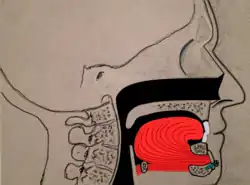

Maxillomandibular advancement

Maxillomandibular advancement (MMA) or orthognathic surgery, also sometimes called bimaxillary advancement (bi-max), or maxillomandibular osteotomy (MMO), is a procedure that moves the upper jaw (maxilla) and the lower jaw (mandible) forward. The procedure was first used to correct deformities of the facial skeleton, including malocclusion. In the late 1970s, advancement of the lower jaw (mandibular advancement) improved sleepiness in three patients. Subsequently, maxillomandibular advancement was used for patients with obstructive sleep apnea.

Currently, surgeons often perform maxillomandibular advancement surgery simultaneously with genioglossus advancement (tongue advancement). The genioglossus advancement pulls the tongue forward to decrease the amount of tongue blockage during sleep. MMA is one of the most effective surgical treatments for sleep apnea, with a high success rate. Nonetheless, the procedure is often used after other forms of treatment have failed (nasal surgeries, tonsillectomy, uvulopalatopharyngoplasty, tongue reduction surgeries). There is a longer recovery when compared to other sleep apnea surgeries, since the bones of the face have to heal into their new position.[20]